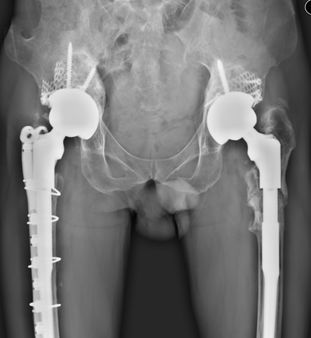

78岁,女性患者,1997年、1998年分别于外院行左侧、右侧全髋关节置换术,术后无痛,功能恢复良好;2011年开始出现右髋疼痛,外院保守治疗,症状缓解不明显,2012年始无法行走,需轮椅代步,来诊X片如上。

2012年5月于我院行右侧髋关节翻修术,2019年右髋翻修术后近7年,左侧初次置换术后22年,2019年1月复查照片,双髋关节假体稳定,位置角度可,患者生活可自理。